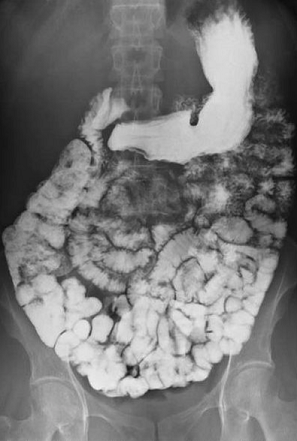

Barium follow through showing small bowel

© By Glitzy queen00 at English Wikipedia, via Wikimedia Commons